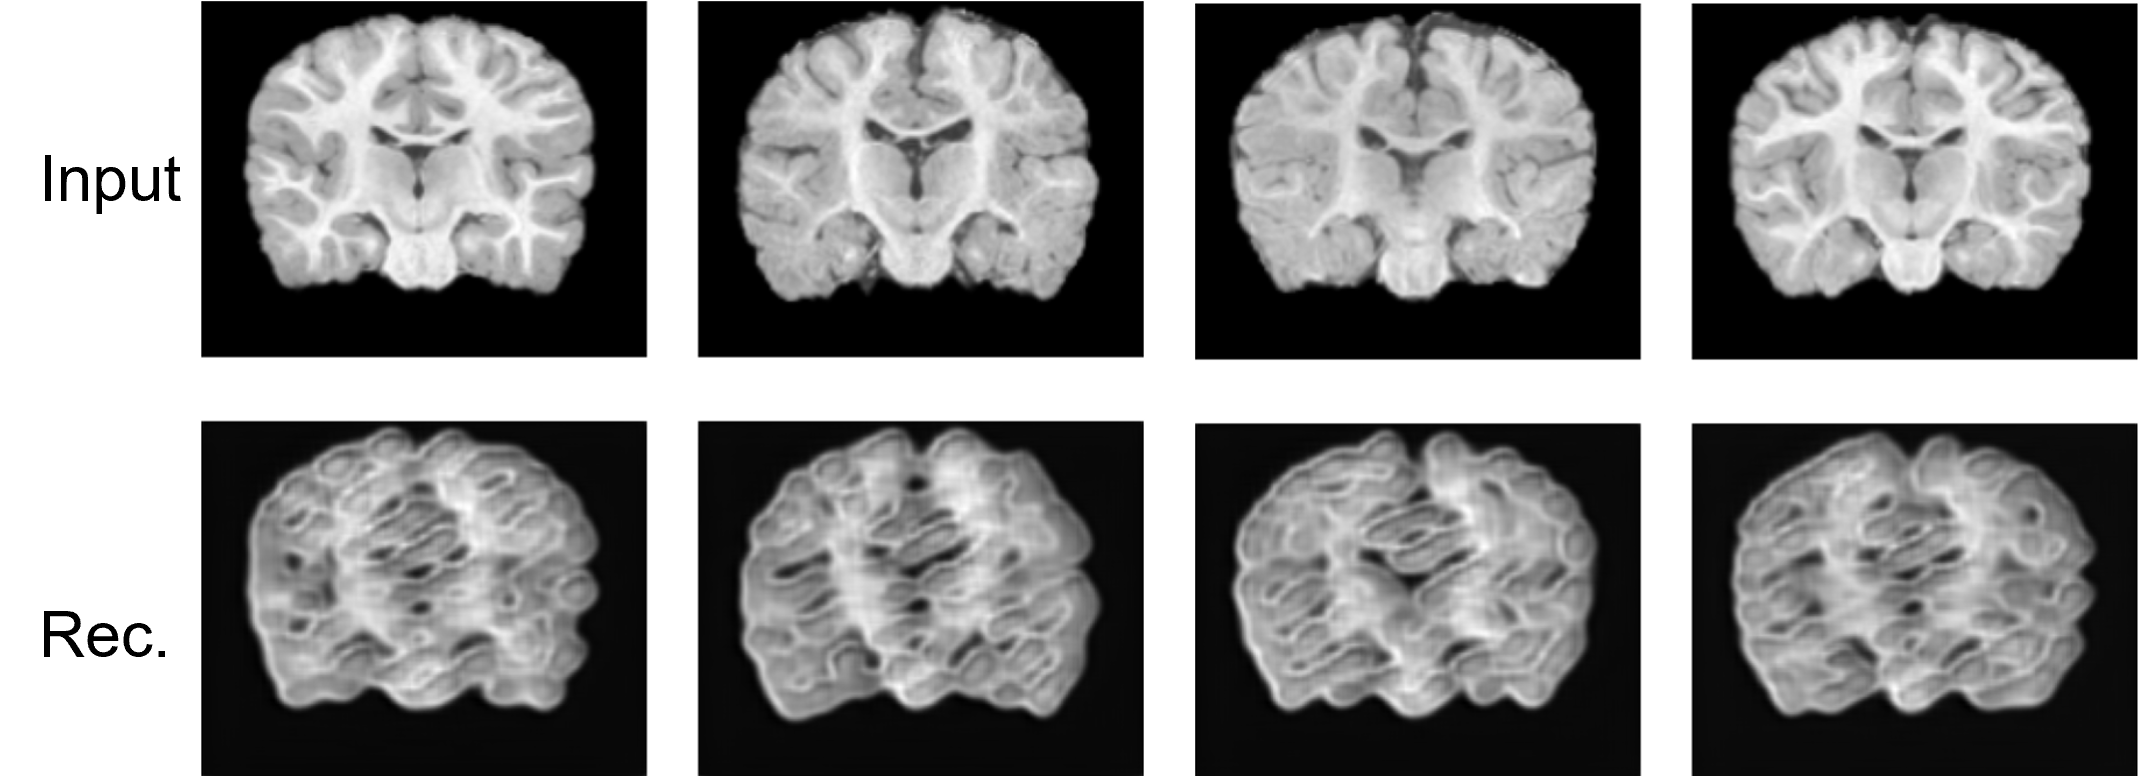

Figure 6: Effect of KL regularization on VAE reconstructions of OASIS-3 brain MR images. The first row displays the input brain MR images, while the second row shows the reconstructed images generated by the VAE.

In Fig. 4 and Fig. 5, we show the reconstruction results of our VAE model. The results in the figure suggest that our VAE model can faithfully reconstruct the input images. From the figure, we can observe that the VAE is able to reconstruct brain images at different developmental stages of infants. This observation aligns with the known characteristic that infant brain images are usually less defined at younger ages and become sharper as the infant grows [1].

AE KL Influence In Fig. 6, we demonstrate that training with a KL regularization significantly affects the performance of the VAE. With a KL regularization, the VAE generates less clear MR images, resulting in blurrier outputs.

AE Batch Size Influence. In Fig. 7, we demonstrate that training with an inappropriate batch size significantly affects the performance of the VAE. When the training batch size is reduced from 256 to 32, the VAE generates less clear MR images, resulting in blurrier outputs. Additionally, the generated images exhibit pattern collapse, where the output patterns become overly similar.